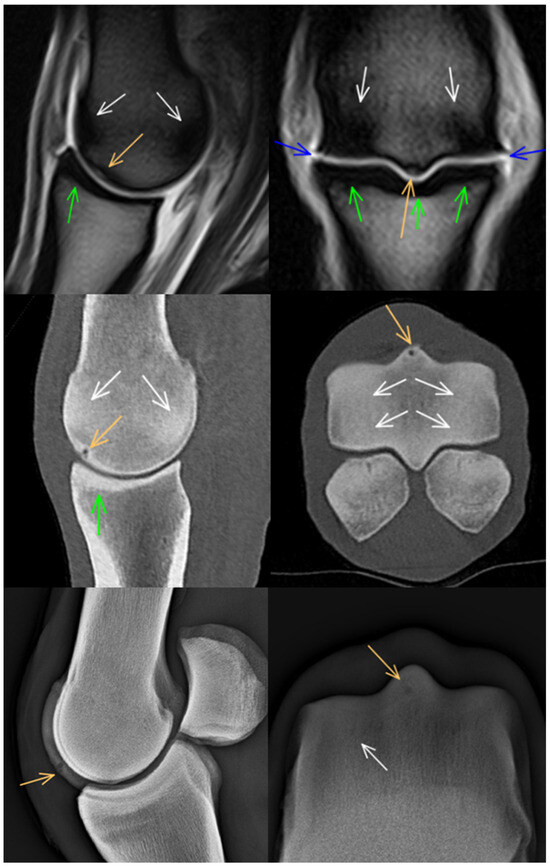

3.2. Proximal Phalanx

3.3. Proximal Sesamoid Bones

3.4. Soft Tissues